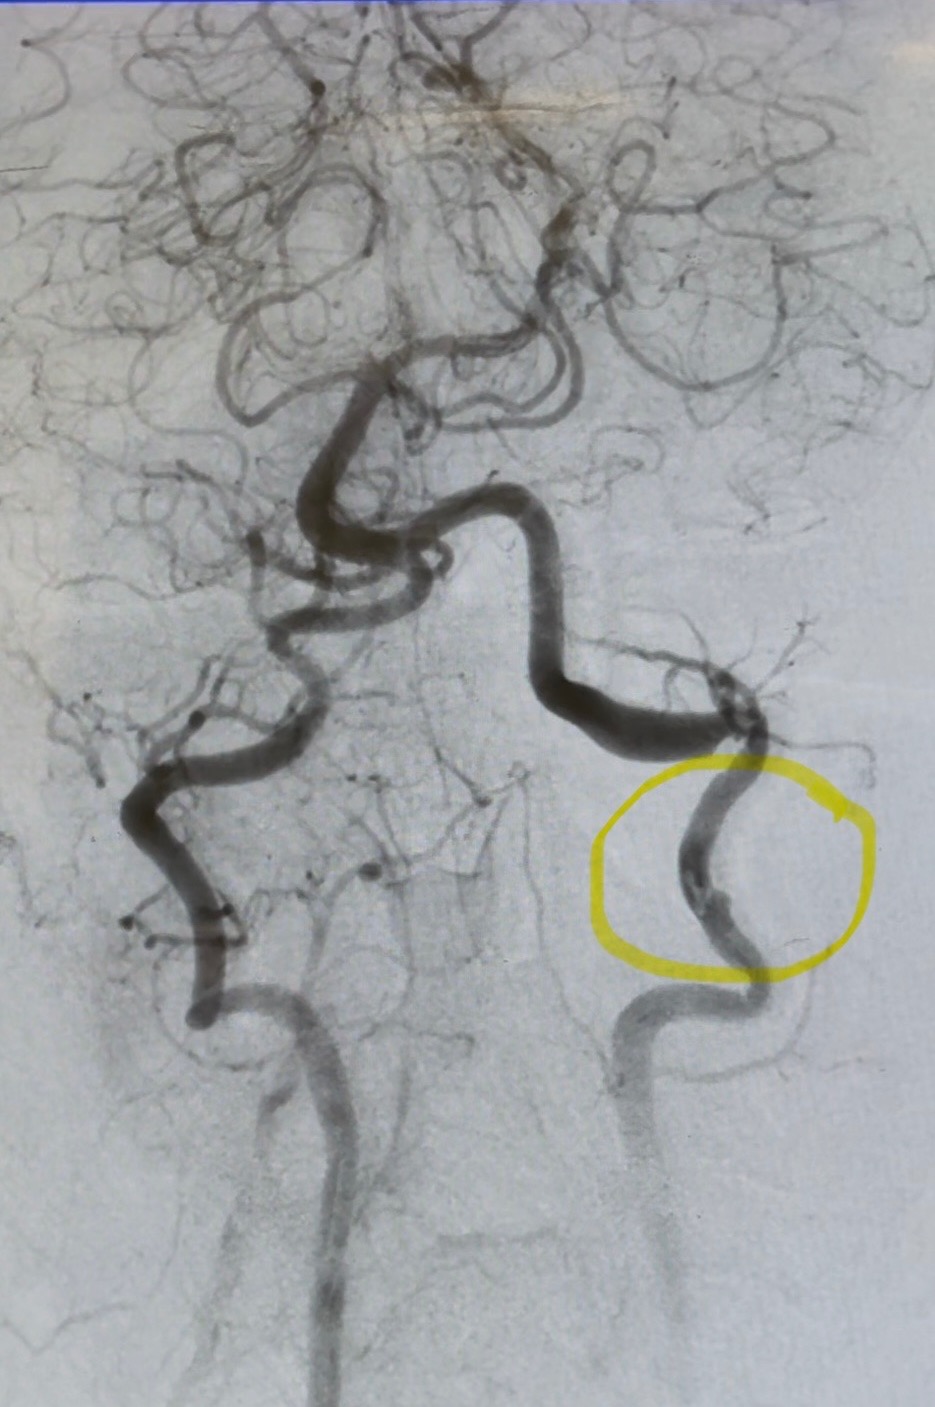

Jason Wolfe recently suffered an embolic stroke and vertebral artery dissection. This sudden and serious medical emergency has left Jason unable to work, and the family is now facing a change in income. The impact of these conditions has not only affected Jason's health, but also their financial stability, as they try to manage both medical needs and everyday expenses.

A special thank you to everyone at St. Bernardine ER, cath lab dream team, ICU, and tele. Jason knows you all moved mountains to save his life.